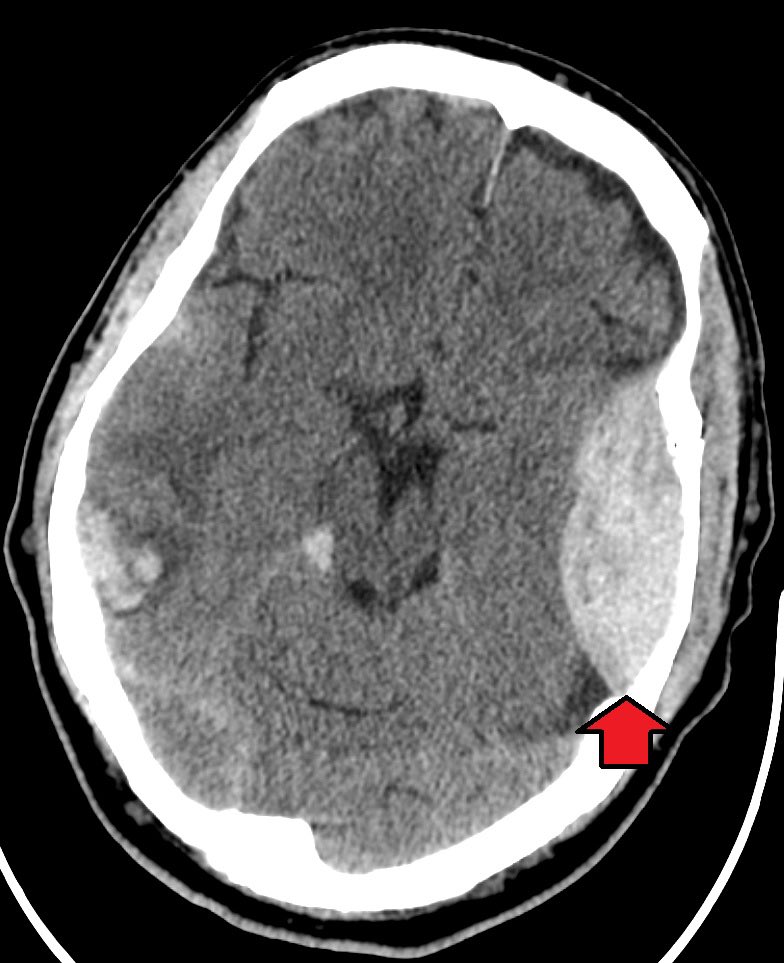

▫️Epidural hematoma🩸🧠

✳️Biconvex (Lens shape) that don’t cross suture lines